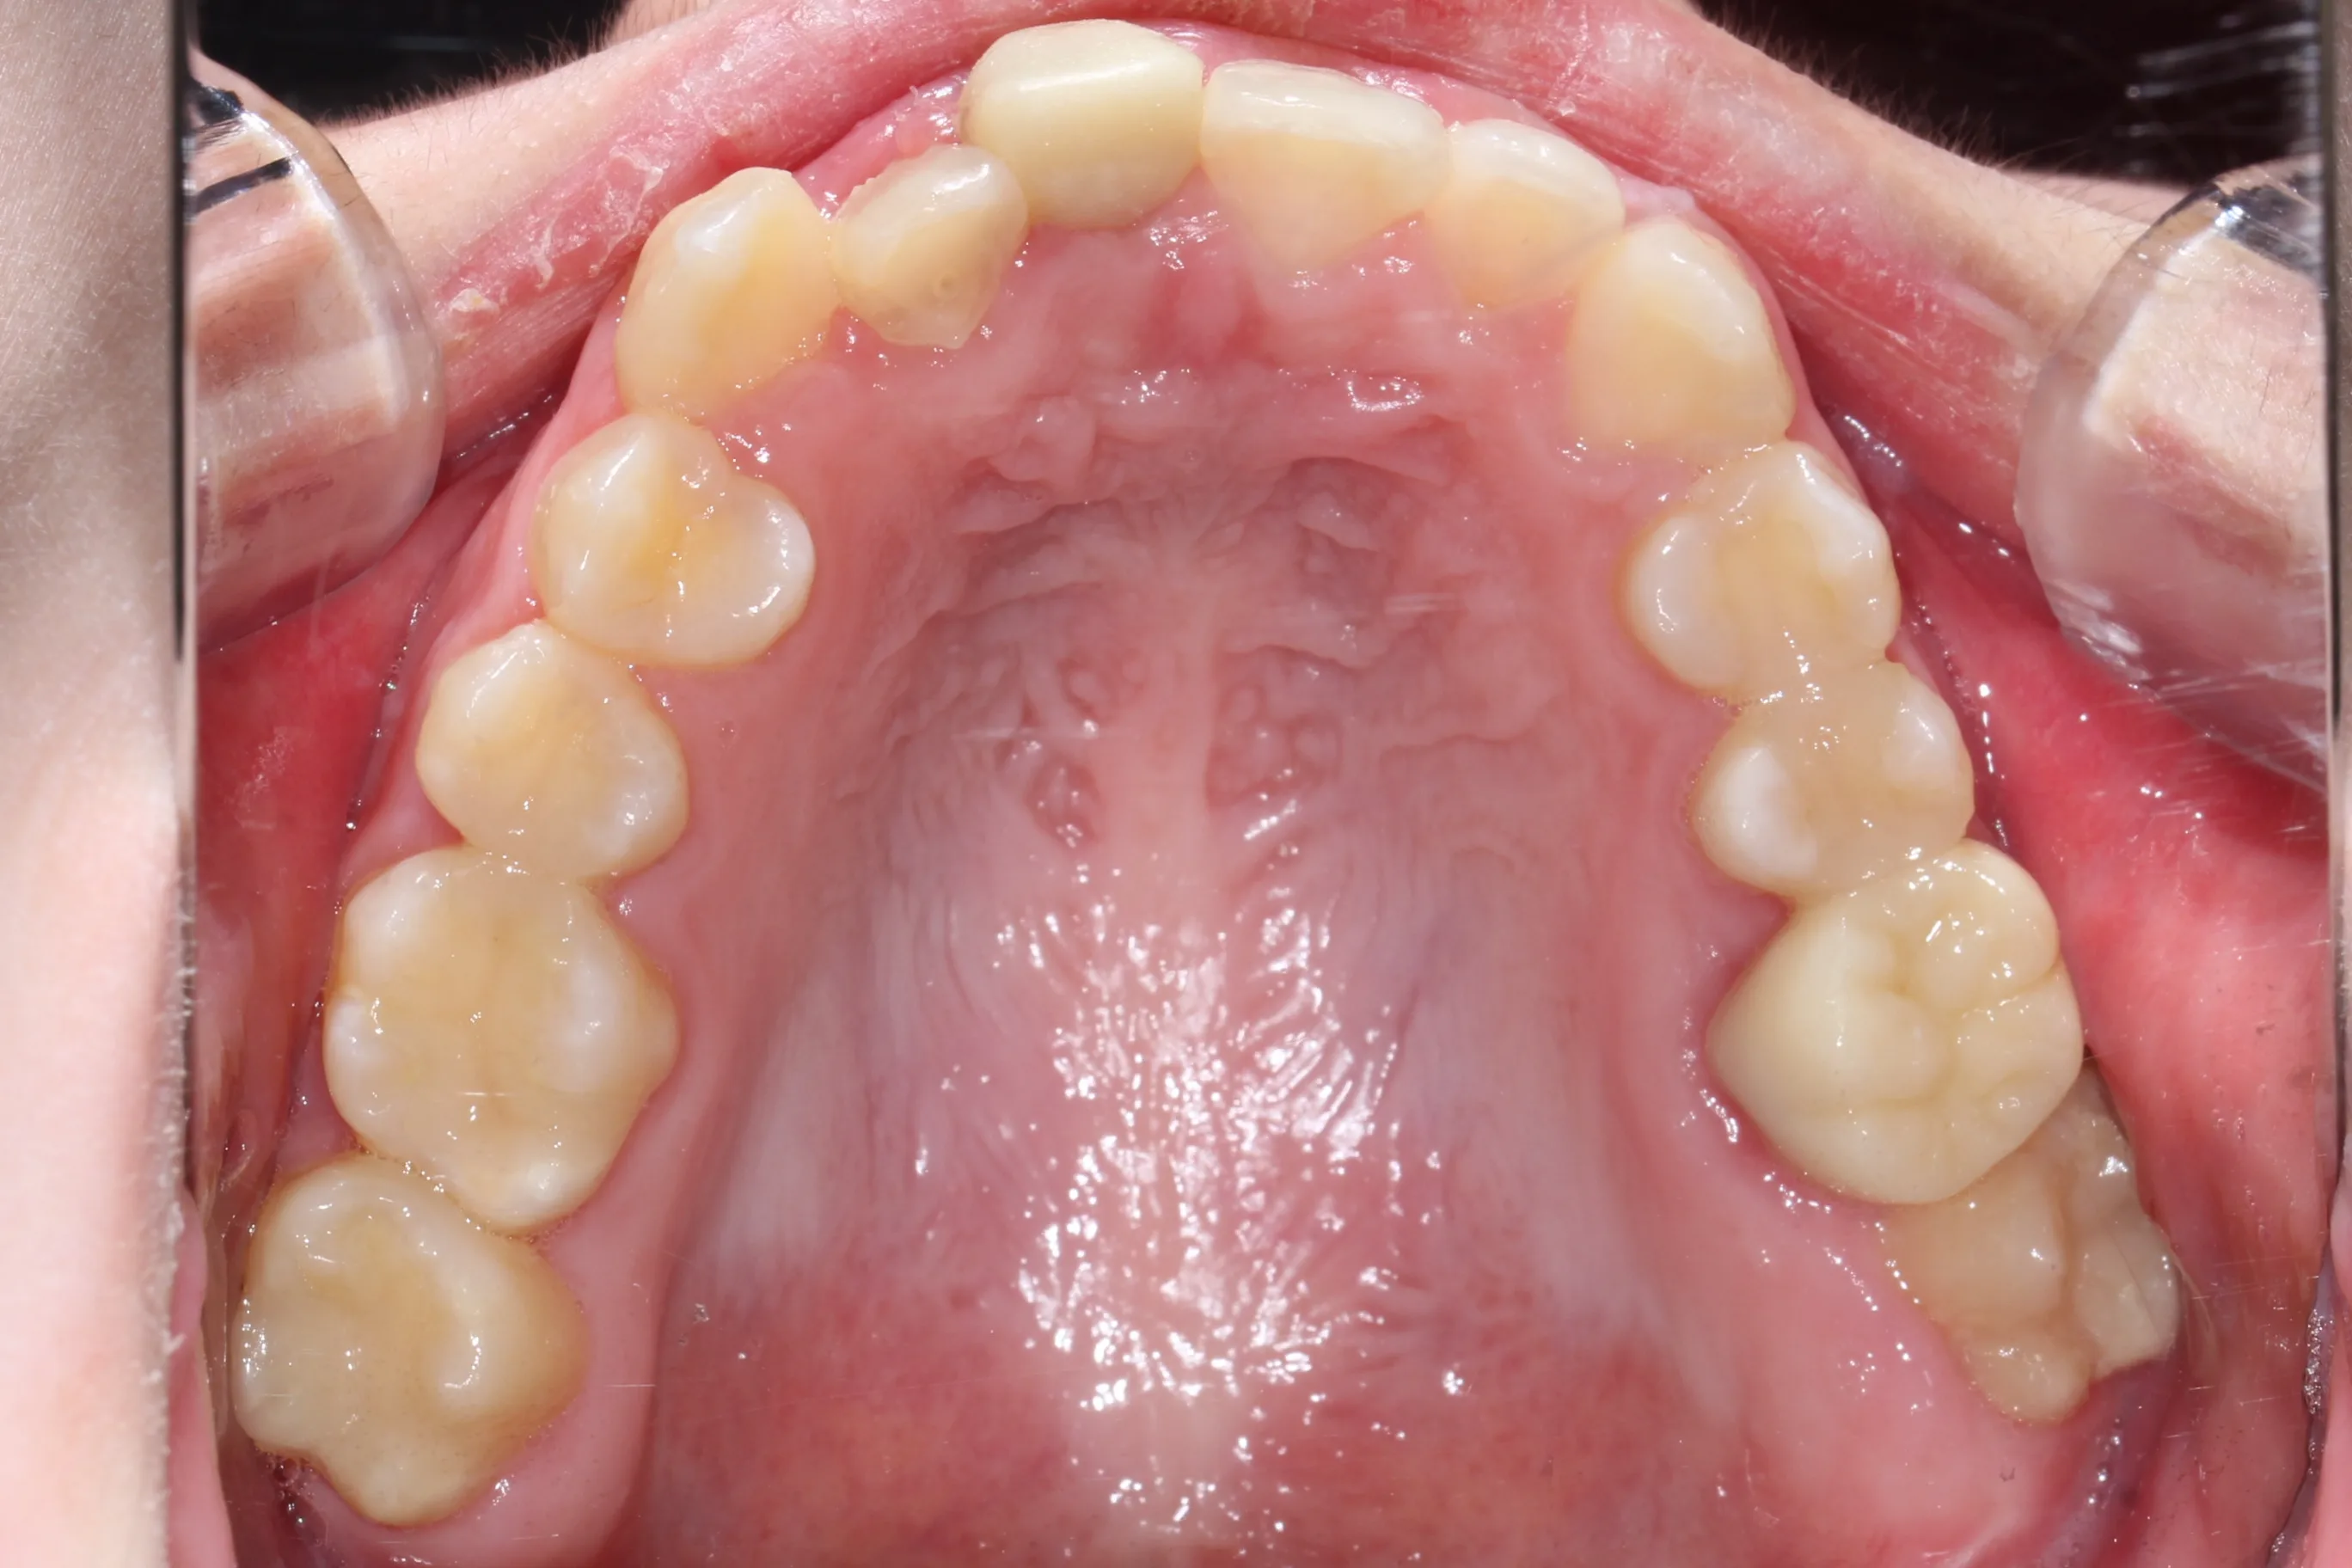

치료후 (After)